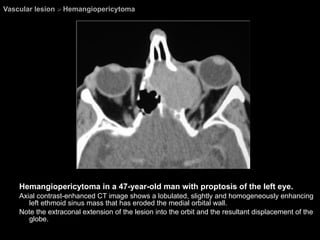

Hemangiopericytoma Rare, slow-growing vascular neoplasms that arise from unique cells called  pericytes of Zimmermann . About 50% of the cases are malignant, and distant metastases. Most such metastases go to the lungs. If not excised completely, these lesions tend to recur, and  wide surgical excision  is the treatment of choice.

Hemangiopericytoma CT & MRI: Slightly less distinct. Erosion of the underlying bone may be present. Marked contrast enhancement.

Vascular lesion  >  Hemangiopericytoma Hemangiopericytoma in a 47-year-old man with proptosis of the left eye.  Axial contrast-enhanced CT image shows a lobulated, slightly and homogeneously enhancing left ethmoid sinus mass that has eroded the medial orbital wall.  Note the extraconal extension of the lesion into the orbit and the resultant displacement of the globe.